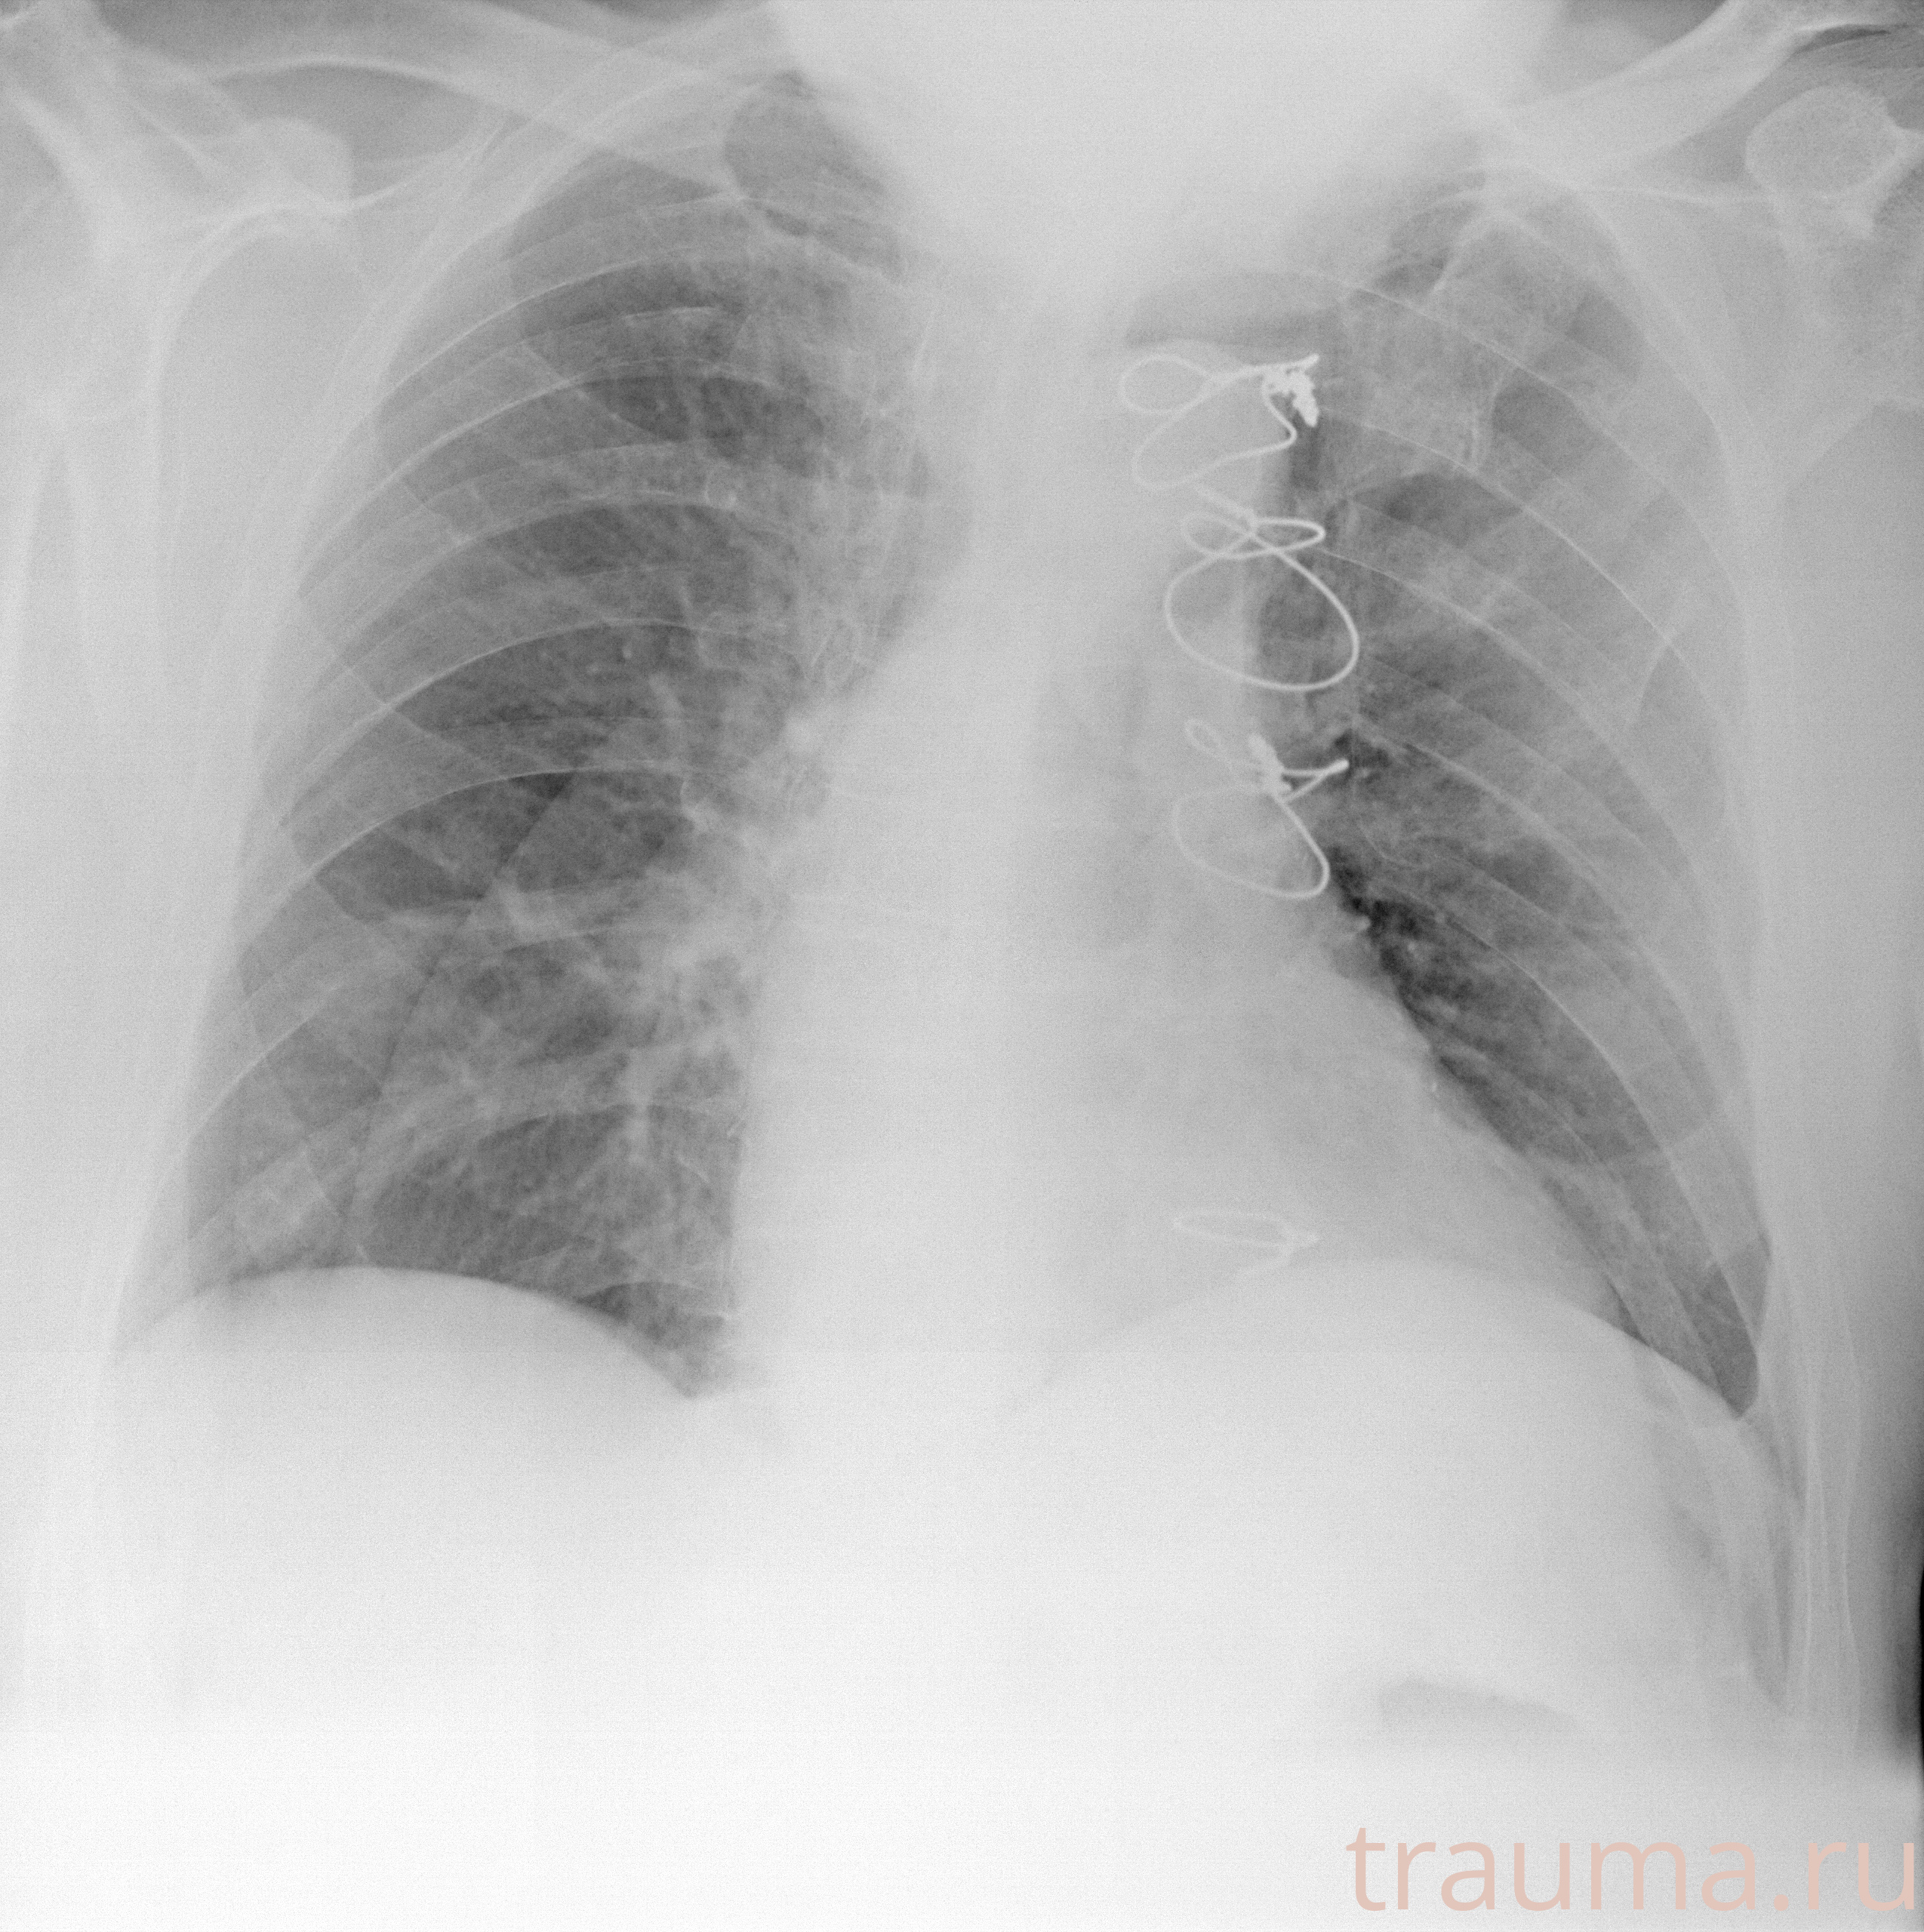

Рентгенограммы

Рентген на дому: по вашему адресу приезжает врач-рентгенолог, травматолог-ортопед с мобильным рентгеновским аппаратом, проводит диагностику травмы или заболевания, делает необходимые рентгенограммы, дает рекомендации по дальнейшему лечению. Получить качественные снимки в домашних условиях возможно благодаря уникальной методике, разработанной МосРентген Центром для института  Склифосовского

Яркость: 1   Контраст: 1   Инвертировать: 0 Увеличение: 1

Перетаскивайте мышь вверх/вниз для контраста, влево/право для яркости. Прокрутка колесом изменяет масштаб. Нажмите Сбросить для возврата к исходному изображению. При увеличении держите мышь в той области, которую хотите рассмотреть.